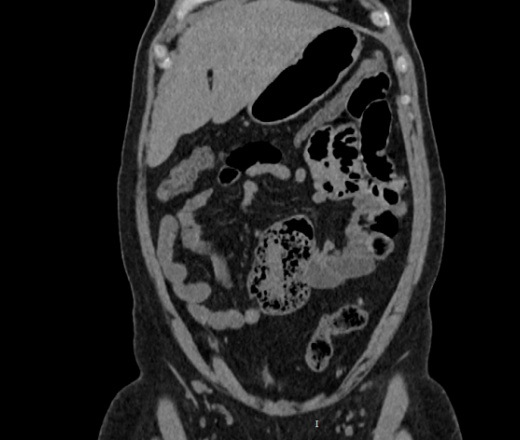

Здравствуйте, женщина 40лет, жалобы на увеличение живота, началось с 2023 года, жалобы на запоры временами и на водянистый стул, подскажите что здесь в области баугиниевой заслонки? инвагинация слепой кишки в подвздошную? что рекомендовать?

В классической рентгенологии такое смещение слепой кишки называли - мобильная слепая кишка.

Описал бы как "кт-признаки болезни Крона (терминальный илеит)", порекомендовал бы колоноскопию с биопсией